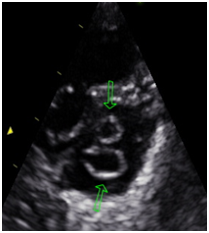

Figure 1 Parasternal short axis.

Figure 2 Parasternal short axis. Presence of 4 muscle Papillary. Double mitral orifice.